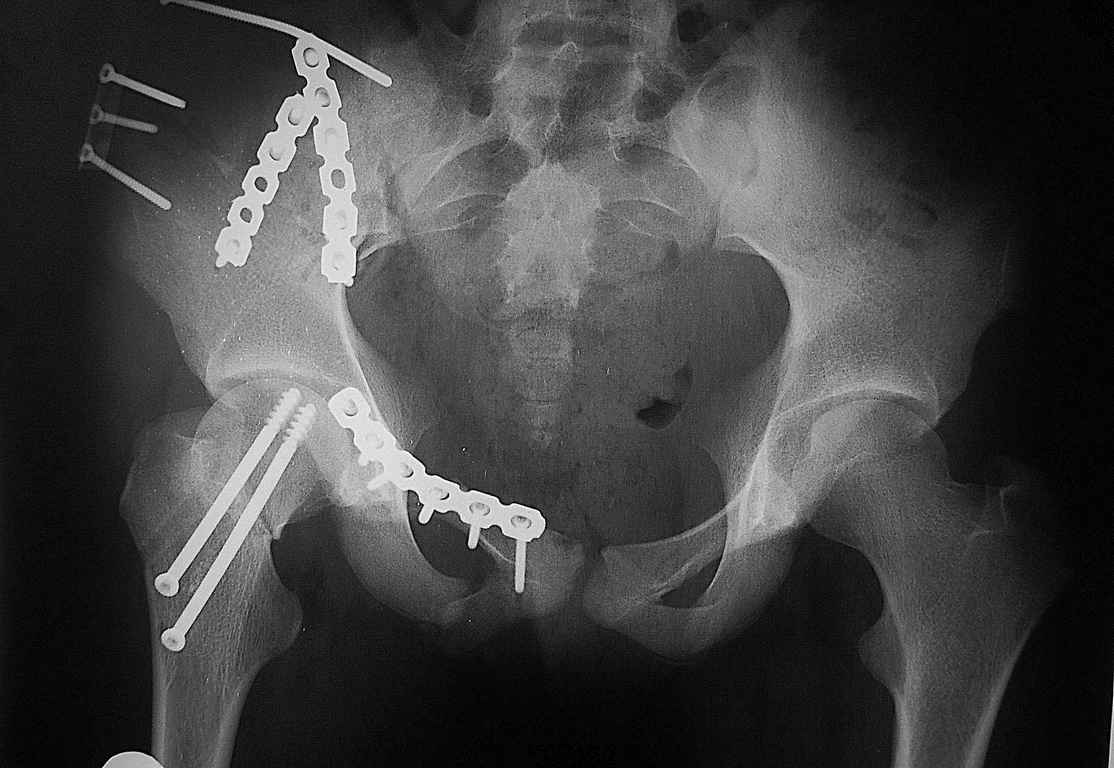

Re: Перелом костей таза

послал Алексей Крылосов 12 Август 2008, 21:59

Уважаемые коллеги огромное спасибо за советы! Больная была прооперирована А.В.Рунковым.